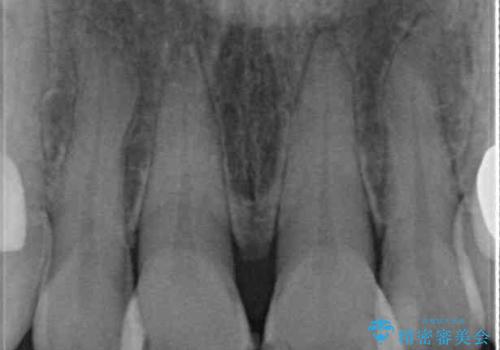

- 何度もコンポジットレジンによる修復を繰り返した結果、冷たいものがしみるようになってしまったとのことで来院された患者様です。

前歯2本が捻れている形態も気になるとのことであったので、虫歯の治療を兼ねて、オールセラミッククラウンにて補綴治療を行うこととしました。

2本とも治療前の歯髄の状態は正常でしたが、補綴治療により歯を大きく削ることになるため、歯髄が炎症を起こすリスクがあることを了解いただきました。